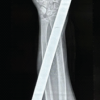

Initial physical examination revealed swelling and transverse widening of the left elbow. The forearm and the wrist were deformed. No open wounds were found. The radial head and the olecranon were palpable laterally and medially. The patient’s hand was well perfused without neurologic abnormalities. Plain radiographs showed a divergent left elbow dislocation associated with ipsilateral ulnar diaphysis fracture, a tearing of epitrochlea (Fig. 1), and a fracture of the radial styloid process (Fig. 2). The elbow joint was reduced under general anesthesia. Because of the radiohumeral instability, the reduction was stabilized with two Kirschner wires through the distal part of the humerus into the radius (Fig. 3). A reinsertion of the medial collateral ligament was performed and the epitrochlea was fixed with two Kirschner wires (Fig. 4). The ulnar diaphysis fracture was reduced and fixed by a screwed plate (Fig. 4) with Kirschner wire-fixation of the radial styloid process (Fig. 5).